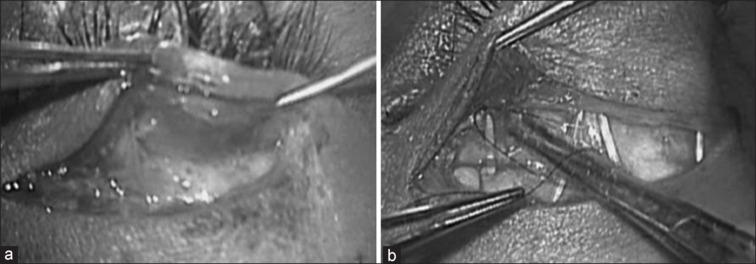

硅胶吊带手术治疗先天性上睑下垂:跗骨管技术。

Silicone sling surgery for congenital ptosis: Tarsal tunnel technique.

This was a prospective, interventional, comparative study conducted on patients with congenital simple severe ptosis. A novel method of silicone rod fixation to the tarsus (tarsal tunnel technique, group 1) was done compared with a conventional technique of silicone rod fixation (suture fixation technique, group 2) in frontalis suspension surgery. A total of 30 patients were randomized into two groups of 15 patients each. Postoperatively, MRD1, vertical palpebral aperture, and eyelid fold height were comparable in both groups till the last follow-up with stability in eyelid position. Patient satisfaction scores showed similar results with good-fair satisfaction grading in 13 patients in group 1 and 11 patients in group 2 at 6 months follow-up. No significant complications occurred in either group. Tarsal tunnel fixation of silicone rods is a novel method in sling surgery with optimal cosmetic and function outcomes. Further long-term studies are needed to validate the results of the technique.

摘要